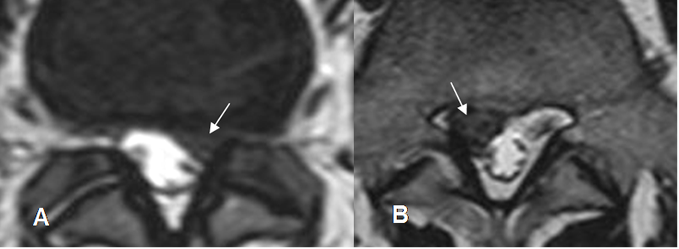

Fig 113. Tipos de degeneración del disco.

A: RM axial en T2. Disco con diferenciación entre el núcleo pulposo y el anillo fibroso.

B: RM axial en T2. Disminución en la señal del núcleo pulposo, persistiendo banda hipointensa central.

C: RM axial en T2. Zona central del disco con señal intermedia.

D: RM axial en T2. Disco hipointenso, sin poder diferenciar el núcleo pulposo del anillo fibroso.

E: RM axial en T2. Disco hipointenso, con pérdida del espacio.

En B existe una hernia extruida y en C y D, una hernia central.